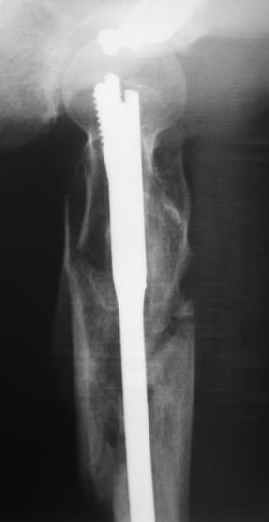

Mike Shnider 17 Сентябрь 2004, 22:59

Все зависит, коллега,от оборудования, которым Вы обладаете.Имеет место метафизарный нестабильный перелом - отсюда и выбор фиксации-это может быть и Gamma nail,Recon nail,да на худой кончик пойдет и Richards DHS или L-plate.Сможете прихватить lesser вертел винтом - чудненько, а не сможете- то футбола не будет,а так по жизни не особенно помешает.

Наверно, можно и так сказать, но можно и тоже самое - 4-фрагментный вертельный перелом. Выбор тот же, но с учетом молодого возраста реконструкционный гвоздь тут более применим. Вот уже наш пример.

В данной ситуации я бы провел остеосинтез при использовании длинного Gamma Nail

Вправление не было бы идеальным но операция закрытым доступом была бы меннее тяжелой так же как и ее последствия .